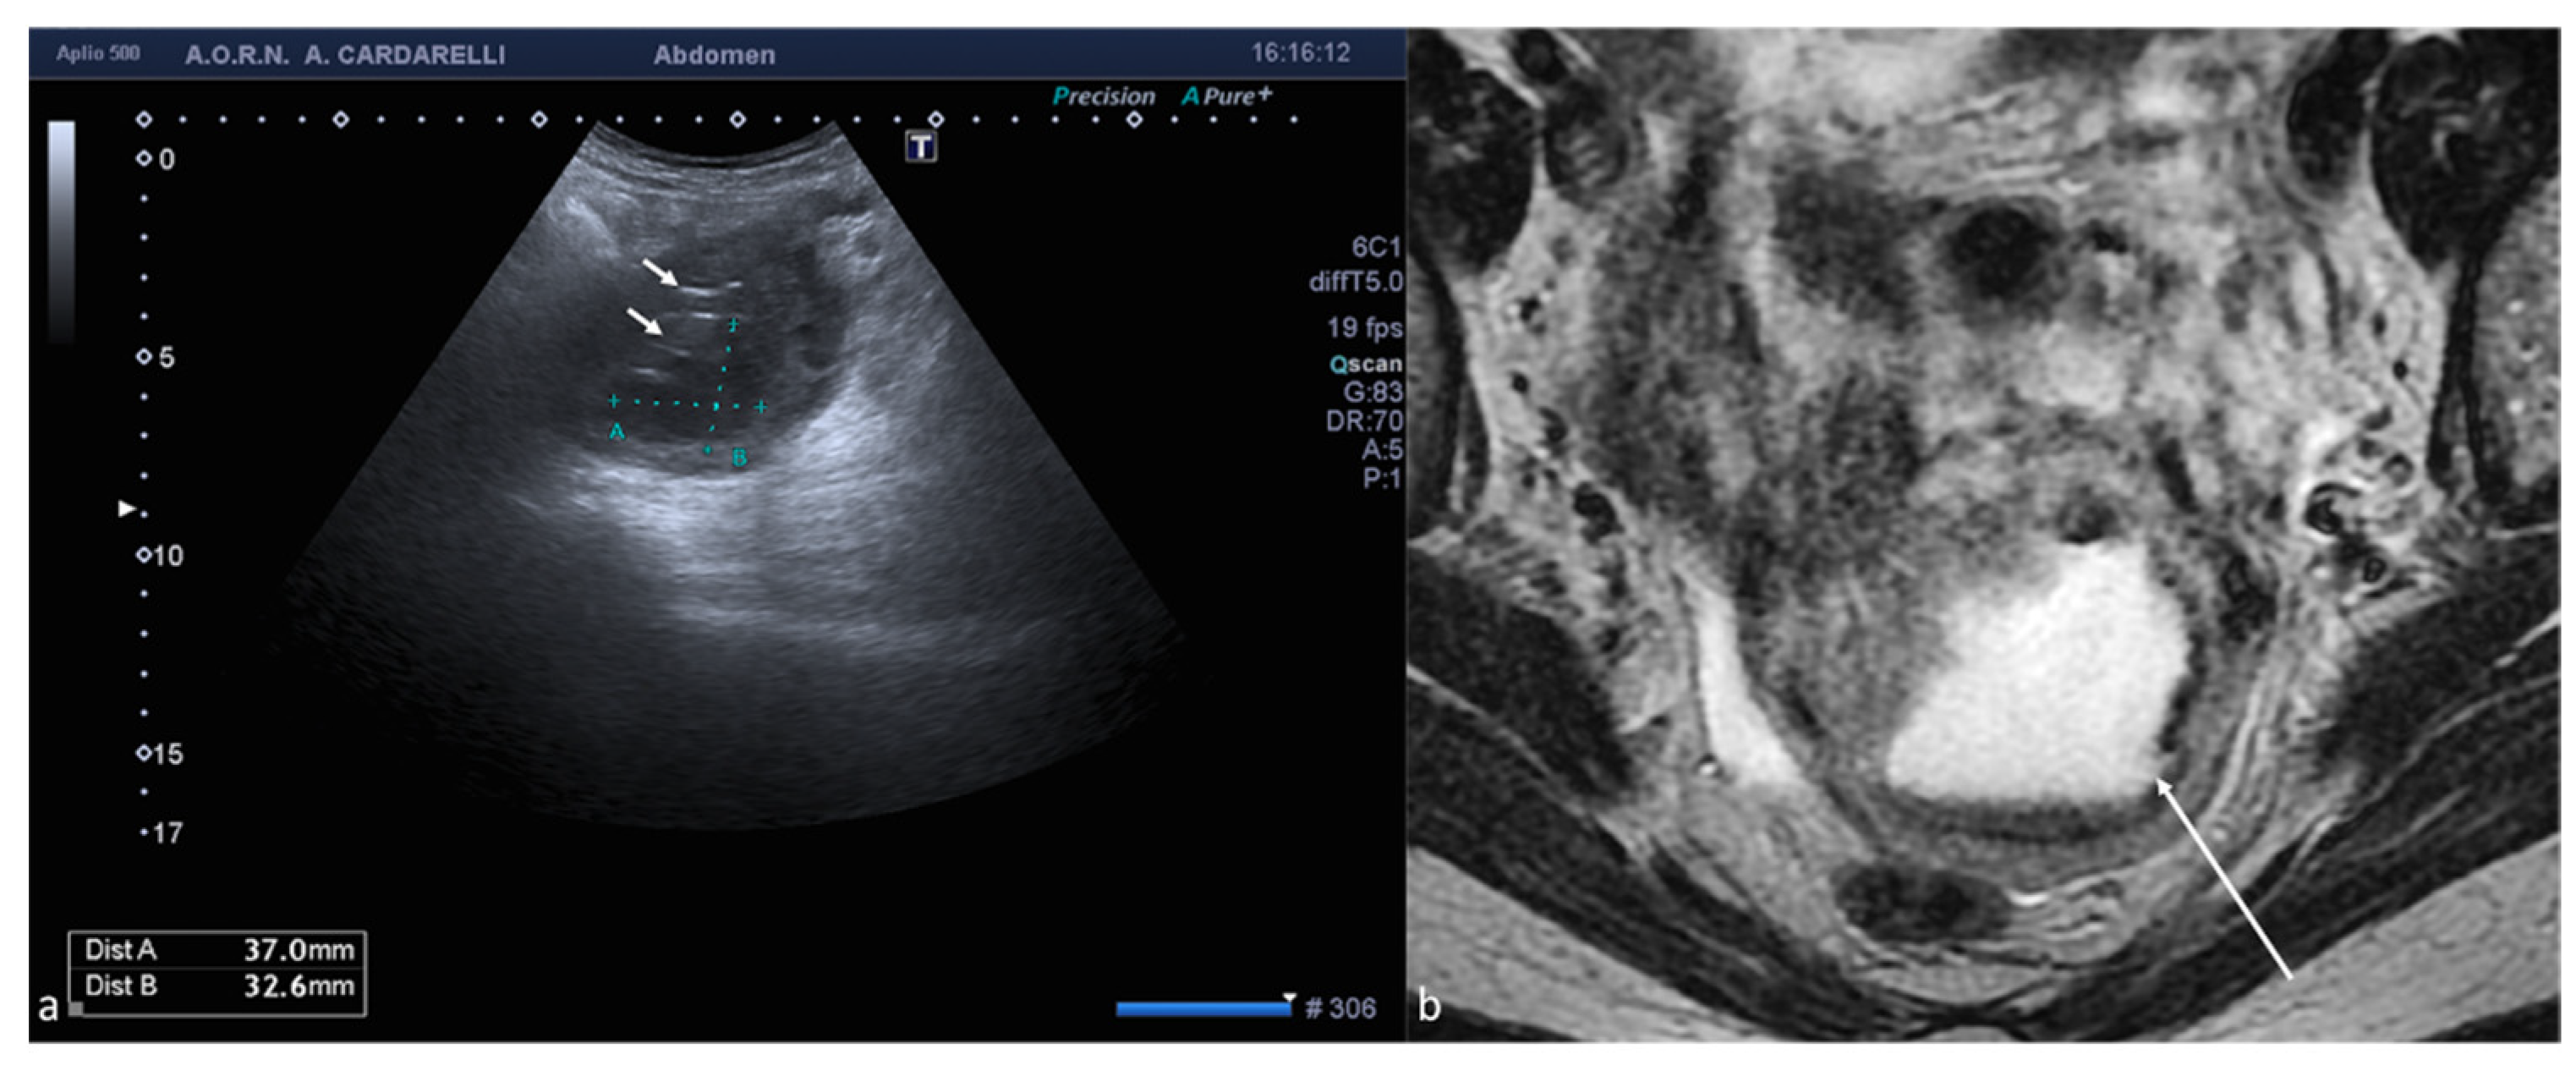

Figure 7. Pyometra. TSA-US scan of the uterus (a) shows a distended uterine cavity containing complex fluid with echogenic foci (short arrows). Axial T2w MRI imaging (b) confirms the diagnosis showing pus collection into uterine cavity.